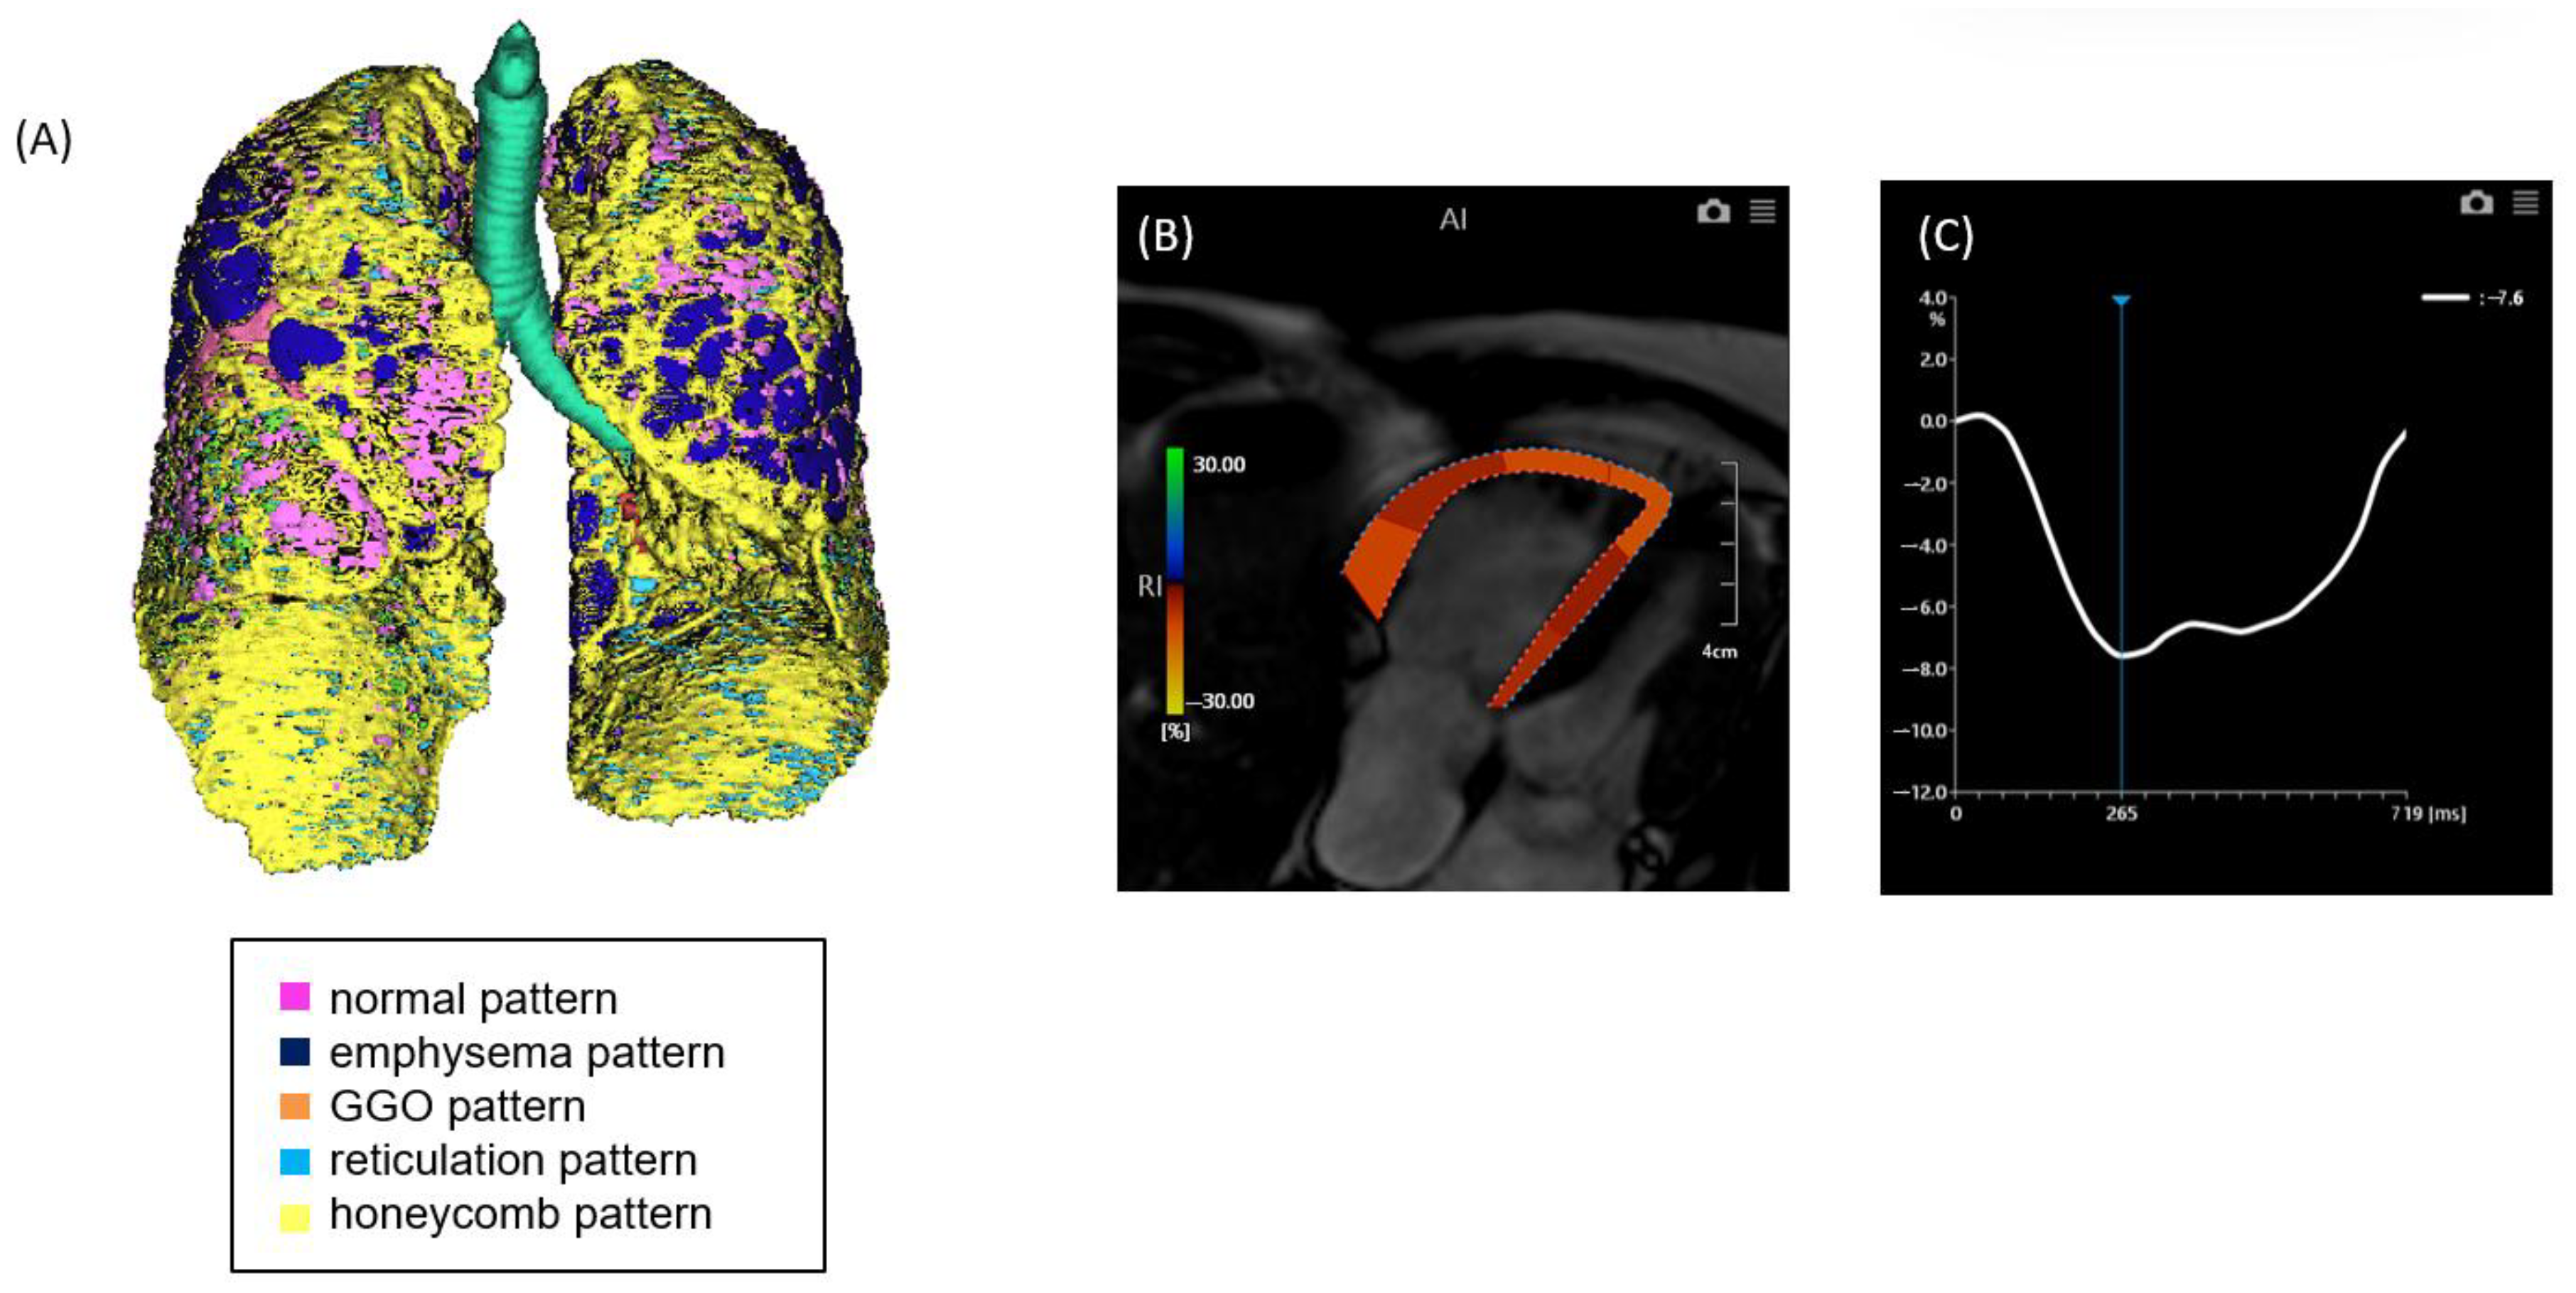

Figure 1. A case of ILD with mild pulmonary fibrosis and preserved right ventricular (RV) strain. (A) Quantitative CT-based 3D reconstruction of lung parenchymal patterns. Normal lung parenchyma (pink), emphysema (dark blue), ground-glass opacity (GGO, orange), reticulation (light blue), and honeycombing (yellow) are segmented. (B) Cardiac MRI showing right ventricular strain analysis using feature tracking. (C) Strain–time curve of the right ventricle showing preserved peak longitudinal strain (−23.0%).

Figure 2. A case of ILD with advanced pulmonary fibrosis and impaired right ventricular (RV) strain. (A) Quantitative CT-based 3D reconstruction of lung parenchymal patterns. Normal lung parenchyma (pink), emphysema (dark blue), ground-glass opacity (GGO, orange), reticulation (light blue), and honeycombing (yellow) are segmented, with extensive honeycombing and emphysema observed. (B) Cardiac MRI showing RV strain analysis with feature tracking, indicating reduced myocardial deformation predominantly in the free wall. (C) Strain–time curve of the right ventricle showing severely reduced peak longitudinal strain (−7.6%).

2.2. CT Image Acquisition and Analysis

Non-contrast chest computed tomography (CT) scans were obtained during full inspiration in the supine position using multidetector CT scanners (Aquilion 64, Aquilion ONE 320, or Aquilion Precision 160; Canon Medical Systems, Japan). The slice thickness was 0.5 or 1.0 mm. The median interval between CT and RHC was 71 days (mean, 88.5 days; range, 0–325 days). CT data were analyzed using the GHNC system, which classifies lung parenchyma into six categories—normal (N), emphysema (E), ground-glass opacity (GGO, G), consolidation (C), reticulation (R), and honeycombing (H)—based on local histogram features and CT attenuation values [9,10]. These categories were predefined using datasets from healthy individuals and patients not included in the current study. The system automatically calculated the volume of each category and the total CT lung volume (CTLV), displaying the results as color-coded overlays. Volumetric data for each category were expressed as percentages of the CTLV. The diseased lung area was defined as the sum of all non-normal parenchymal patterns, including GGO, honeycombing, reticulation, emphysema, and consolidation (Figure 1 and Figure 2). In this study, the extent of fibrosis was quantitatively assessed using the percentage of diseased lung area—defined as the sum of GGO, reticulation, honeycombing, consolidation, and emphysema—relative to the total CT lung volume (i.e., expressed as a percentage of the entire lung). This quantitative measure was used as a surrogate marker for the stage of pulmonary fibrosis.